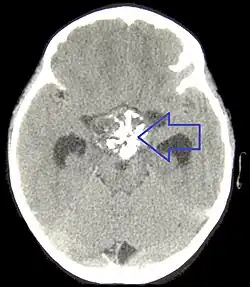

Badania obrazowe

W tomografii komputerowej guz ma postać torbielowatej, hipodensyjnej masy, często z obecnymi nawapnieniami, położonej w linii środkowej. Część lita guza może ulegać wzmocnieniu kontrastowemu.